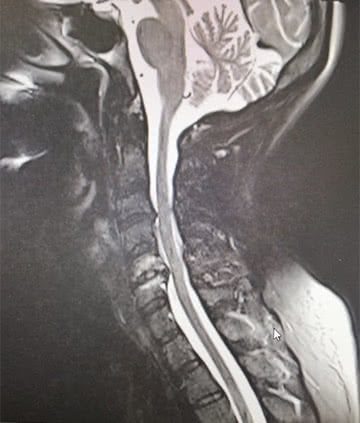

Mielopatía Cervical

Es la alteración de las funciones de la médula espinal por la compresión que sobre ésta ejercen las estructuras de la columna cervical.